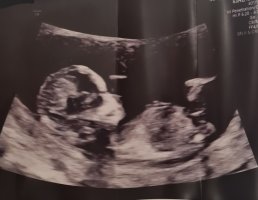

Tidlig jente, men det kan fremdeles skje ting.Dette ble tatt for et par uker siden, 11+6 ca ble det sagt/målt til. Kanskje litt tidlig men hva tror dere ?![]()

Men sikkert fordi jeg ikke helt skjønner hvor jeg skal seHvis du ser på den hvite lange streken som er helt til høyre på bilde ca midt midten på enden av magen liksom. Hvis det er en gutt så pleier den å stikke litt mer opp og av og til vil man se at det ligger flere små litt mer grå strekeroppå den hvite som man kaller stacking. Så må man se på vinkelen fra toppen på de strekene som man kaller for nub, og gjennom blæra parallelt med ryggraden. Nå hører jeg selv hvor avansert det høres ut, men om man ser på litt flere bilder av gutter og jenter så er det lettere å se forskjell. Jenter har ofte en hvit lang nub også er blæra høyt oppe mot nuben, mens på gutter er den litt lenger nede. Her så ser man en bitteliten sort prikk høyt oppe som er blæra. Så dette er en jenteÅåå,jeg synes ikke det var så lettMen sikkert fordi jeg ikke helt skjønner hvor jeg skal se

ahaaa!!! Gratulerer så mye med ei litta jente!! Så stas!Hvis du ser på den hvite lange streken som er helt til høyre på bilde ca midt midten på enden av magen liksom. Hvis det er en gutt så pleier den å stikke litt mer opp og av og til vil man se at det ligger flere små litt mer grå strekeroppå den hvite som man kaller stacking. Så må man se på vinkelen fra toppen på de strekene som man kaller for nub, og gjennom blæra parallelt med ryggraden. Nå hører jeg selv hvor avansert det høres ut, men om man ser på litt flere bilder av gutter og jenter så er det lettere å se forskjell. Jenter har ofte en hvit lang nub også er blæra høyt oppe mot nuben, mens på gutter er den litt lenger nede. Her så ser man en bitteliten sort prikk høyt oppe som er blæra. Så dette er en jente![]()